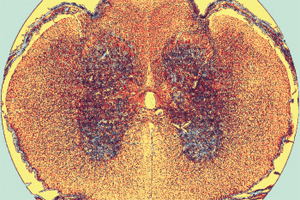

It is made up by two kinds of tissue.

- At the center is the nucleus or grew matter and it contains cell bodies as well. It is organized into four roots: two dorsal, which receive information through sensory neurons spread throughout the body, and two ventral roots, which contain the cell bodies of the motor neurons, which sent signals to the skeletal muscles.

– Surrounding the grew matter is the white matter, formed by axons of neurons that are connected in two ways: ascending, which carry incoming signals to the brain regarding physical sensations the body is feeling, and descending, which transport outgoing signals from the brain to the skeletal muscles regarding voluntary movements.